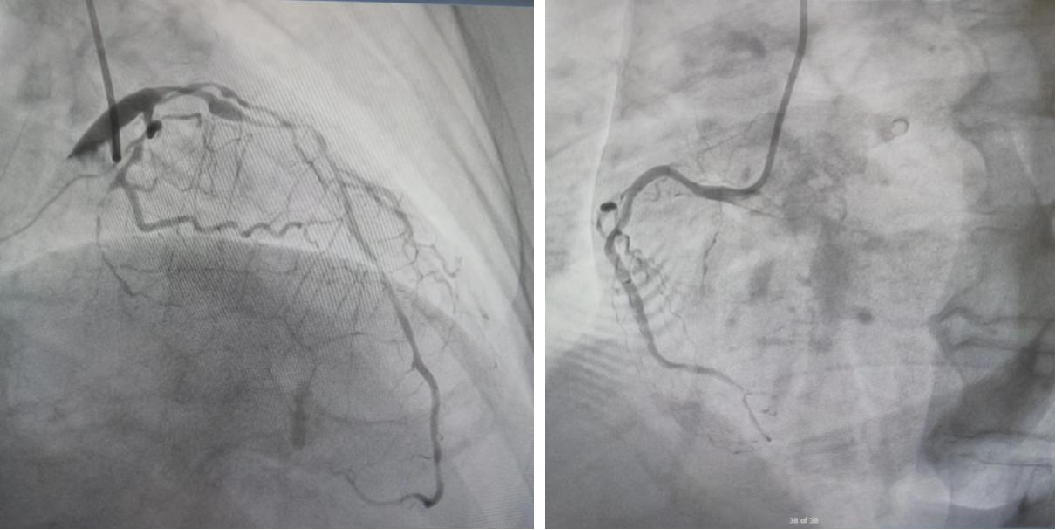

冠脉造影探查心力衰竭原因:LM未见明显狭窄;LAD近段瘤样扩张,近中断钙化长病变,最重狭窄90%;LCX近段弥漫性长病变,最重狭窄90%,远端次全闭塞。RCA近段狭窄60%,远端次全闭塞,建议冠脉搭桥手术,患者及家属拒绝。

image.png

最终诊断:1、冠状动脉粥样硬化性心脏病(缺血性心肌病,心力衰竭,心功能III级)2、颈动脉粥样斑块,3、高血压病(一级,极高危),4、2型糖尿病,5、陈旧性脑梗死,6、慢性肾脏病(CKD 3期)。7、子宫切除术后,8、高脂血症。